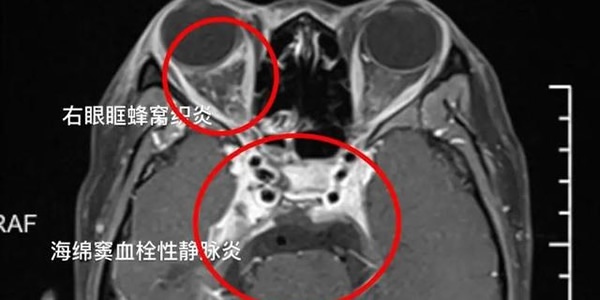

1、女孩挤痘引发颅内感染:19岁的宁波宁海女孩小杨因为鼻梁上长了一颗痘痘,就将它挤掉,结果引发颅内感染,患上海绵窦血栓性静脉炎住进了医院。

医生介绍,以嘴唇画一条直线,以鼻根部为一个点,连接起来的面部区域叫做危险三角区。这种因为在危险三角区挤痘造成的深部感染,如果没有得到及时治疗,轻则住进医院ICU,重则可导致患者死亡。